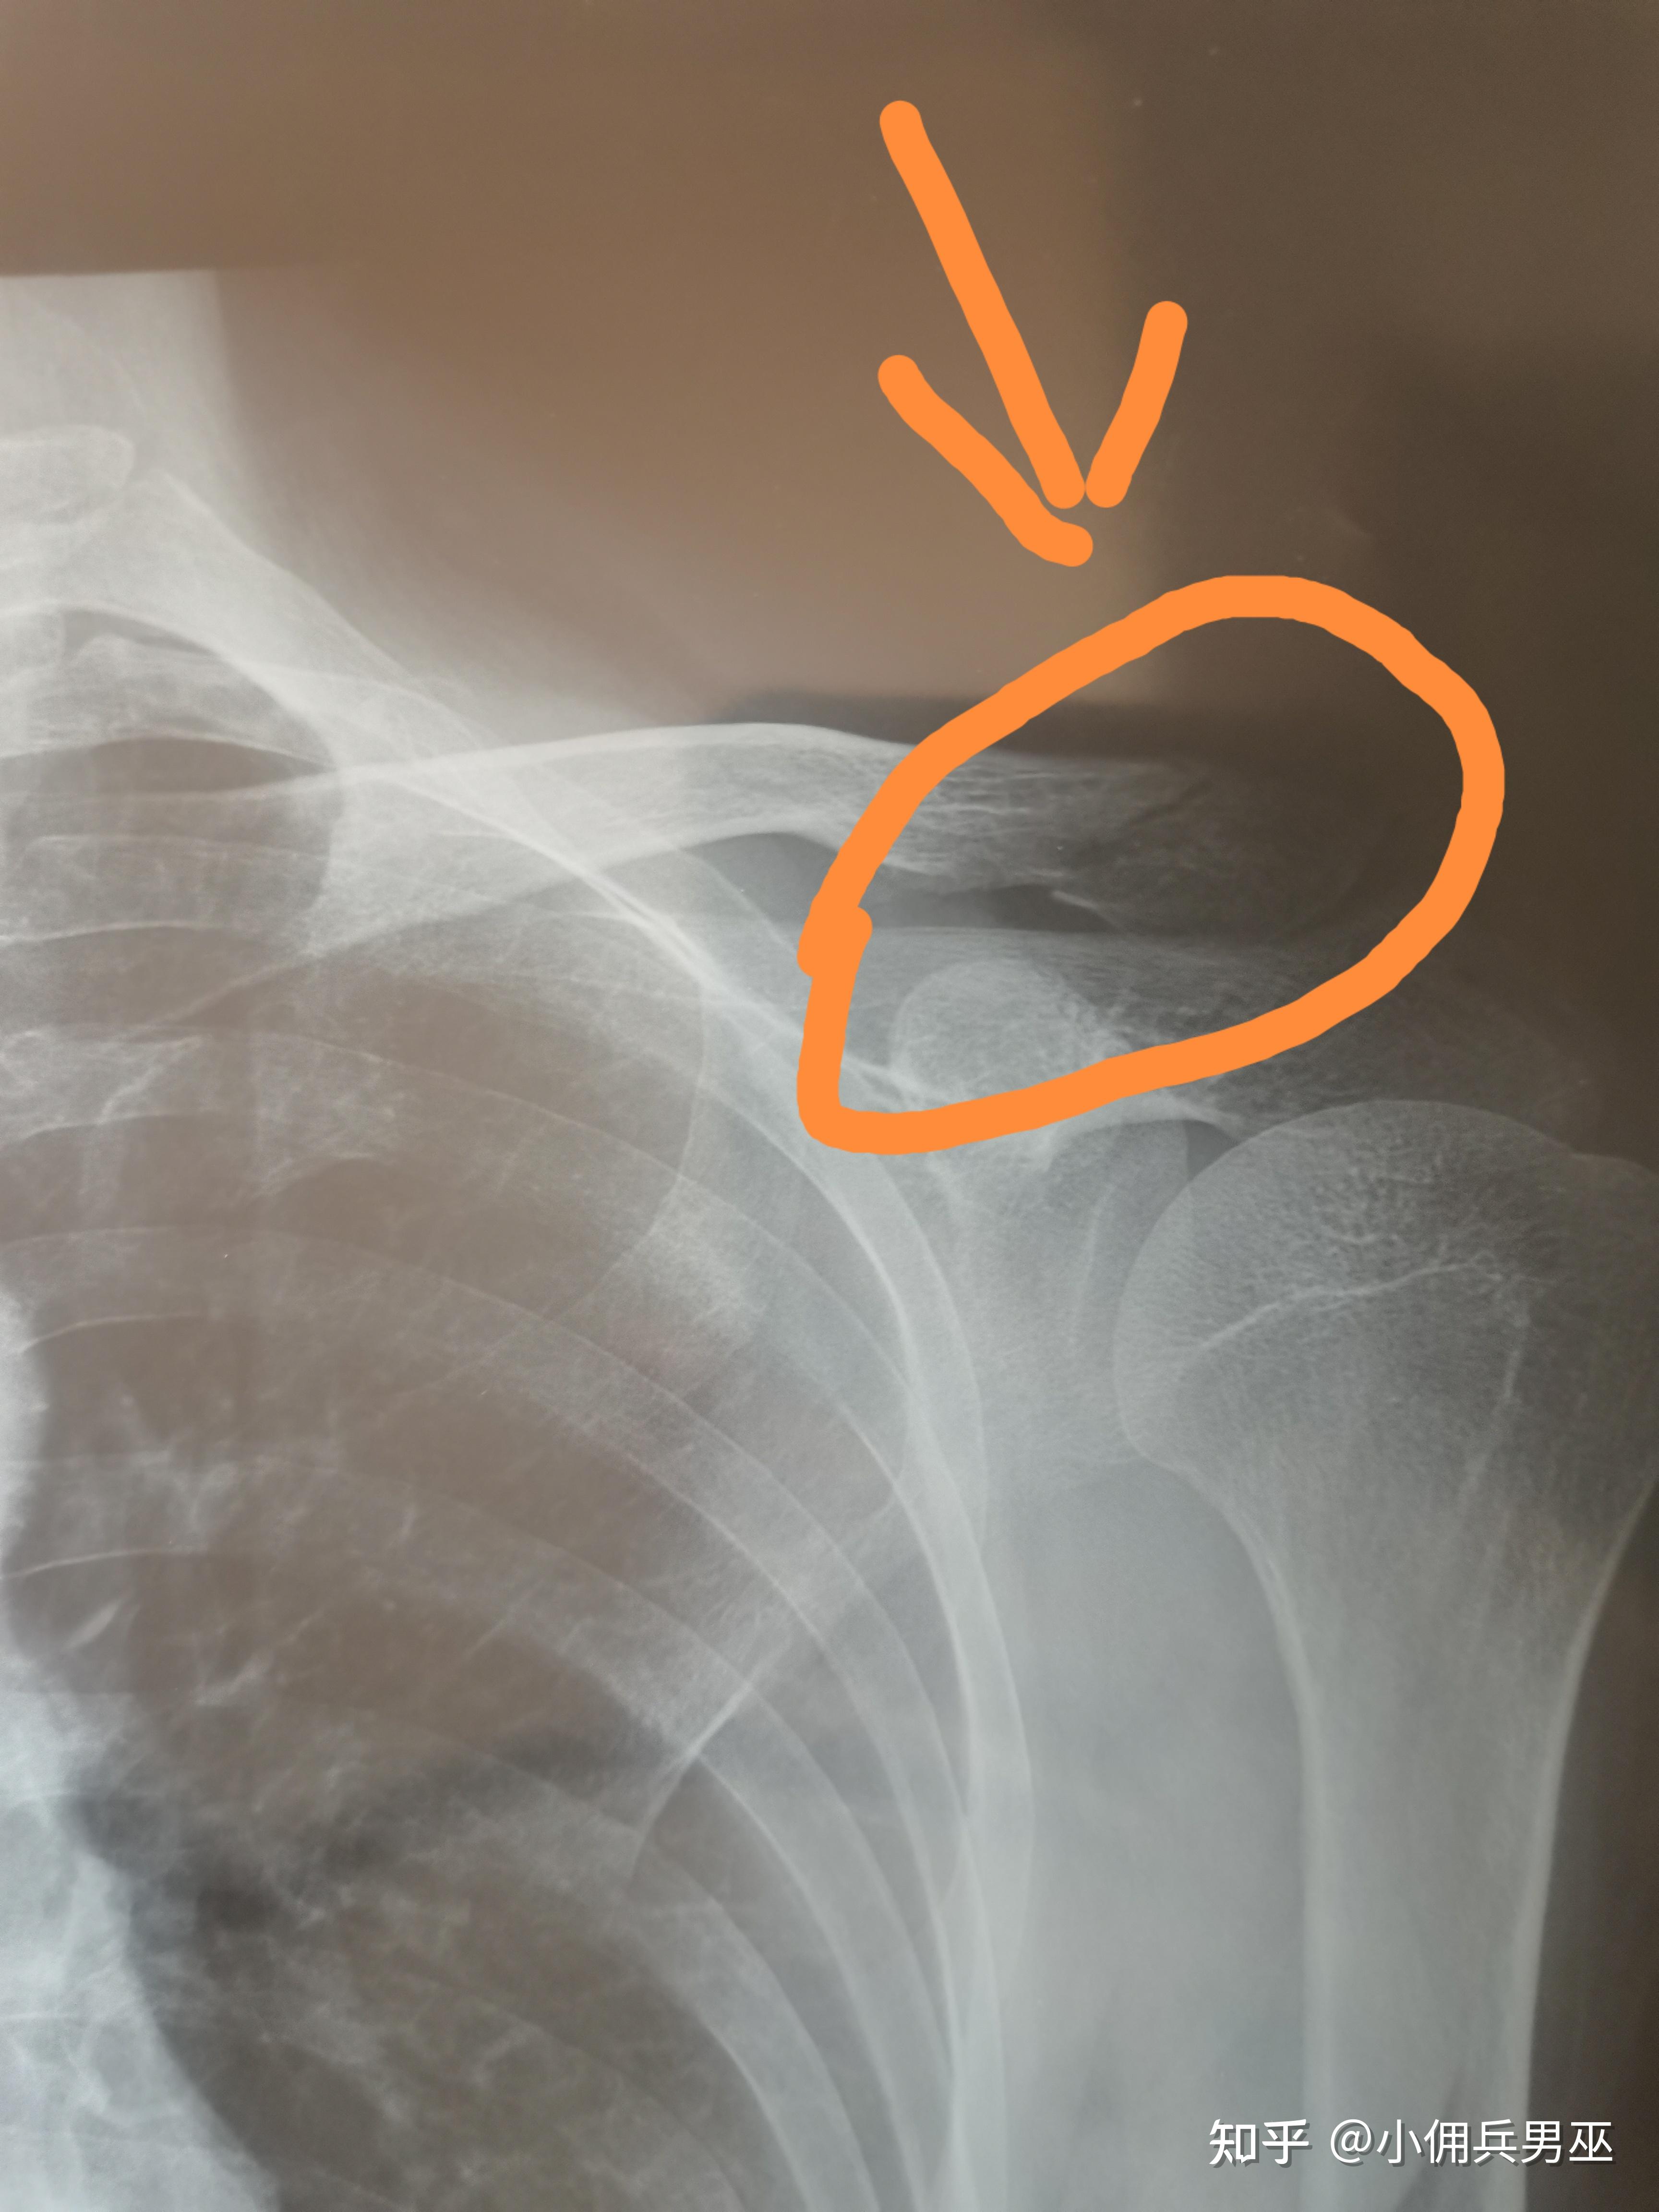

锁骨骨折治疗标准里为什么不能成角?